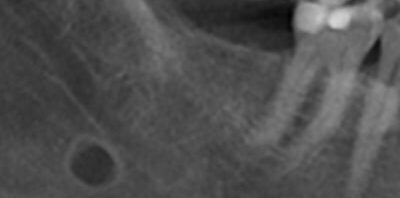

74-year-old man with a mandibular lesion

A 74-year-old man was referred to the oral surgeon by his dentist because of a mandibular lesion in the right mandible.